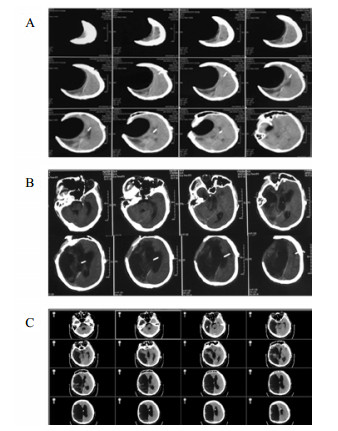

病例3,患者男,76岁,因“突发头痛昏迷,动脉瘤栓塞脑室引流术后半年余,脑积水分流术后3个月”入院。入院体查:GCS 7分,植物状态,双巴氏征阳性。V-P分流调压阀压力为1.0,脑积水虽已行分流术,但脑室仍明显扩大。拟诊:左前交通动脉瘤栓塞术后,脑积水V-P分流术后,持续性植物状态。脑室压力低于外耳道连线5 cm, 持续外引流脑脊液100~200 mL/d,同时去枕卧位,腹带加压包扎,适当增加补液量和扩脑血管改善脑微循环,力求增加颅内压和脑顺应性。脑室压力逐渐上升,然后调压至0.5,期间多次复查未见脑室大小明显缩小;但患者出现对威胁有眨眼反应,偶尔能对视觉对象定位,转为微小意识状态。发病4年后,即80周岁时,因为肺部感染而再次入院,控制肺部感染期间,考虑脑室仍扩大状态,予按压分流阀600次/d,患者意识显著上升,能主动要求饮食并表达喜好,能和家属互动做简单游戏。随访头颅CT见脑室较前有所缩小(图 5C)。

| A:第一次入院CT(脑出血栓塞和脑室外引流后);B:常规治疗后脑室扩大仍明显;C:2018年7月5日随访 图 5 病例3 CT |

病例2,女,60岁,2017年10月以“动脉瘤夹闭和脑内血肿清除术后6个月,意识进行性下降2个月余“入院。入院时植物状态;查体:GCS 8分,双瞳孔3.0 mm,对光反应灵敏,双侧病理征阴性。右侧额颞部颅骨缺损大。入院头颅CT示脑室扩大。诊断为:右前交通动脉瘤术后、脑积水、头皮下积液、右额颅骨缺损、持续性植物状态(图 3)。

| 右侧额颞部颅骨缺损7 cm×9 cm,双侧脑室和三脑室扩大 图 3 2017年10月12日病例2的CT |

入院后于2017年10月30日行“颅骨修补+V-P分流术”。术后将分流管压力逐步调至0.5。患者术后意识无明显改善,复查CT示脑室仍显著扩大。观察2周后病情同前,遂将储液囊外接引流,每日引流量约200 mL,持续3 d,未见行为学及影像学明显变化。加大引流至每日300 mL,持续3 d后,患者自主睁眼增多;引流量增至每天400 mL左右,患者能呼唤下睁眼和视觉追踪。而停止脑脊液外引流后,患者则退步到引流前水平。决定通过按压储液囊促进脑脊液引流(按压600次/d),持续10 d后,睁眼时间延长但仍无意识。考虑到患者意识水平和引流量明显相关,增加按压储液囊频率至1 500次/d,患者又能呼唤睁眼,但CT未见脑室明显缩小。随后增加按压至2 000次/d时,偶尔能出现遵嘱活动,复查CT示脑室结构较前稍有缩小,但脑室仍显扩张。动态观察患者的行为学变化和反复CT随访,逐步升至4 000次/d,患者可表达简短言语,但脑室仍略扩大。随后每月按压次数递增1 000次直至6 000次,复查CT示脑室结构明显缩小(图 4A);患者意识显著改善,能简短正确对答。2018年6月病情稳定后,逐渐减少到3 000次/d, 并复查头颅CT(图 4B)。患者意识完全恢复,交流言语思路清晰,搀扶能行走。

| A:2018年3月27日头颅CT,此时6 000次/d,脑室系统明显缩小;B:2018年9月15日头颅CT,3 000次/d 图 4 病例2头颅CT |